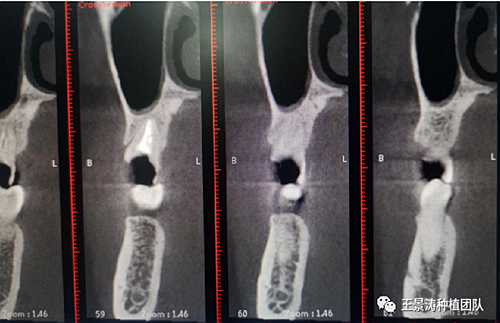

下述病例則是15區(qū)域的即刻種植,15因牙冠折斷于齦下,無法樁核冠修復(fù),則考慮種植修復(fù)。但拍攝CBCT后發(fā)現(xiàn)根尖距上頜竇底距離較短?;颊邽槟贻p女性,無全身系統(tǒng)疾病且可利用上頜竇底與根尖皮質(zhì)骨雙側(cè)皮質(zhì)骨固位,且此位置可通過頰側(cè)軟組織減張技術(shù)獲得嚴(yán)密封閉牙槽窩。因其根尖距上頜竇距離較低,遂拔除15后行上頜竇內(nèi)提升,埋入式種植,最終修復(fù)的完成。